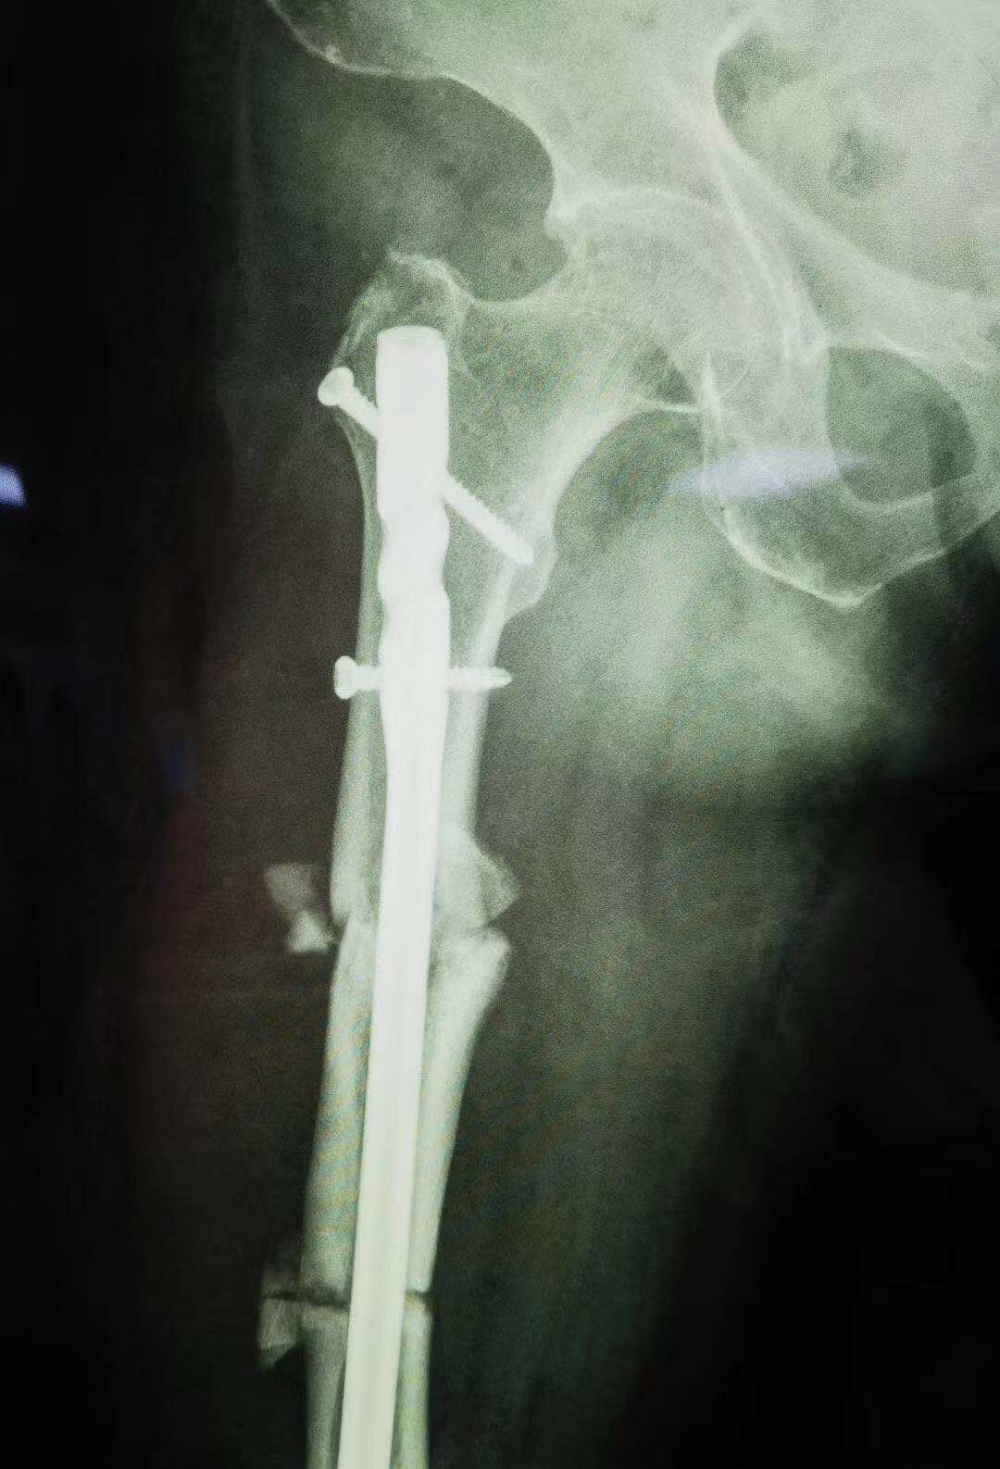

術(shù)后拍攝的X光片

骨傷一科主任汪永泉帶領(lǐng)團(tuán)隊(duì)多次會(huì)診,拿出較為可行的三套方案,對(duì)每套方案進(jìn)行細(xì)致詳盡的評(píng)估。最終在取得家屬同意的情況下,確定在7月28日,由骨傷一科主任汪永泉、管床醫(yī)生樊煒聯(lián)合為患者進(jìn)行手術(shù)。

據(jù)汪永泉主任介紹,此次手術(shù)很成功,術(shù)后通過(guò)觀察,病人目前沒(méi)有血管的危象,而且整個(gè)神經(jīng)沒(méi)有牽拉,而且病人整個(gè)下肢體長(zhǎng)度,也基本達(dá)到術(shù)前預(yù)想的恢復(fù)長(zhǎng)度。